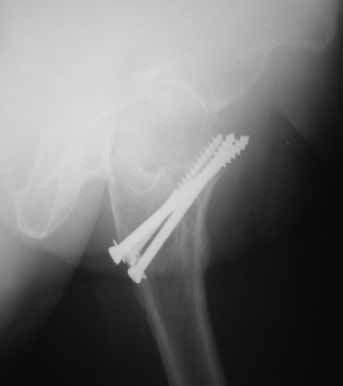

На консультации вот такие снимки. Больная 72 года. упала в быту 26 декабря 2010г.

Оперирована 30 декабря 2010г. в одном из стационаров края. Назначили дополнительное обследование, а пока хотелось-бы услышать мнение по-поводу возможностей сохранения головки. Больная из льготного контингента, т.е. современные констукции и эндопротез маловероятны.